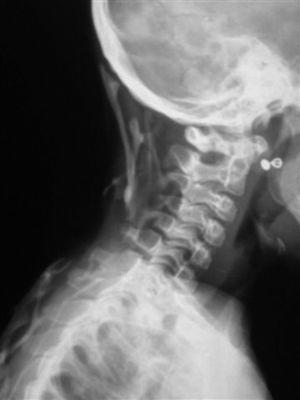

En la última serie ósea completa realizada se objetivaron múltiples calcificaciones a nivel de partes blandas sin evidente participación ósea, siendo más llamativo a nivel cervical con afectación del esternocleidomastoideo y trapecio (fig. 2). También en ambos pectorales (fig. 3), en columna dorsolumbar de D1 a D5, en L2, en el sacro derecho, en ambos psoas (fig. 3) y en el glúteo derecho. Existían mínimas alteraciones de osificación a nivel de metáfisis distal de ambos fémures y proximal de ambas tibias y osteoporosis generalizada con escoliosis dorsolumbar.

Figura 2. Calcificaciones cervicales. Espacios intervertebrales conservados.